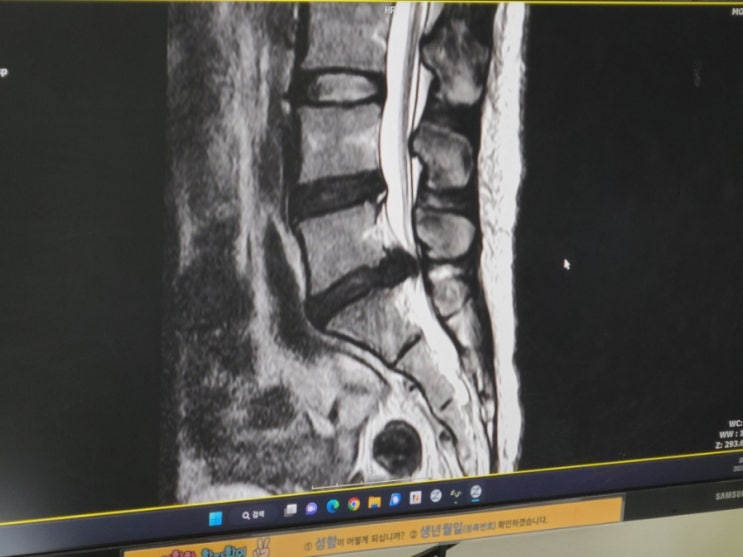

L5-S1 허리디스크 파열, 마미총 증후군으로 인한 미세현미경 감압술 수술 후기

L5-S1(5-1번) 허리디스크 파열로 인한 마미총증후군(말총증후군)으로 인천성모병원에서 미세현미경 감압...